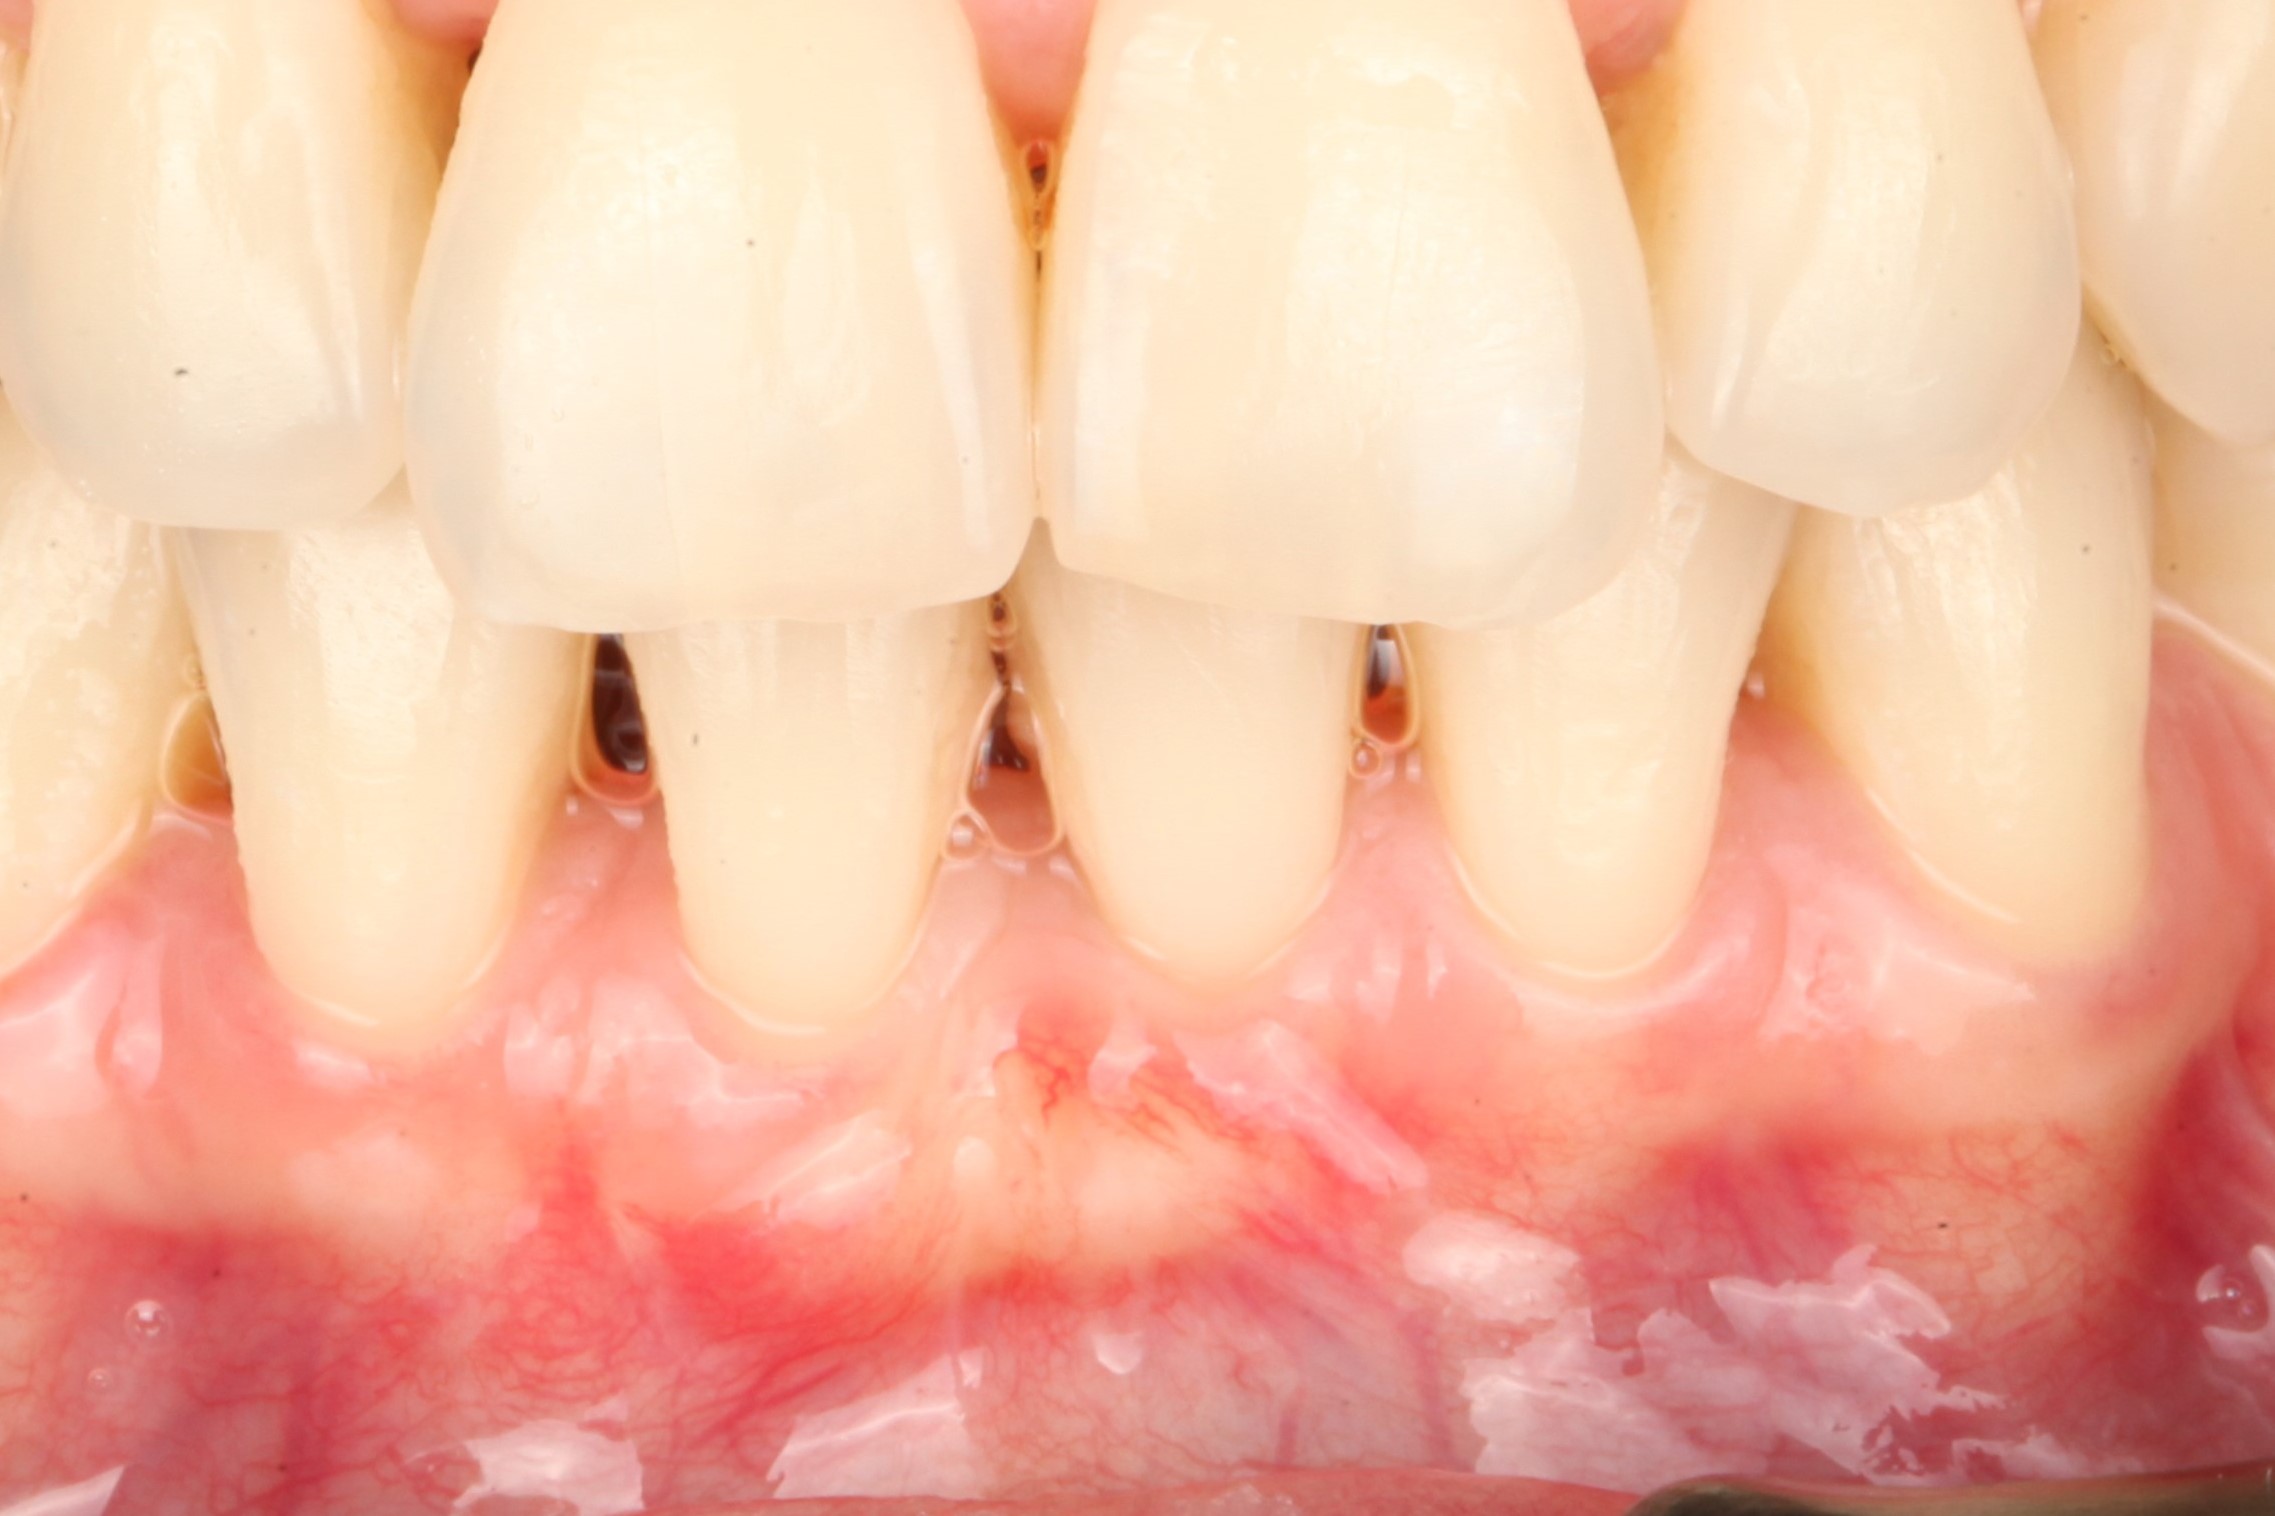

тонкий биотип десны, рецессия 2 мм на зубе 4.1